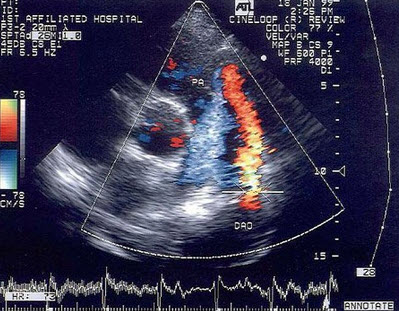

45、单项选择题

如图,初步超声诊断为()

A.二尖瓣返流

B.三尖瓣返流

C.主动脉瓣返流

D.肺动脉瓣返流

E.以上均不是